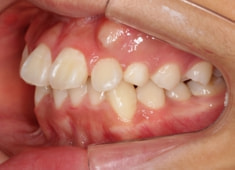

治療前